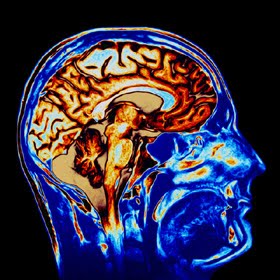

Unutkanlığı önleyen besinler

Beynin sürekli aktif olması, dikkat ve konsantrasyon açısından zengin olması yediğimiz yiyeceklere bağlı. Kısaca özetlemek gerekirse protein, karbonhidrat, vitamin ve minerallerden oluşan bir beslenme programı ile beynin performansını artırmak mümkün. Balık, yeşil yapraklı sebzeler, lahanagiller ve tahıl içerikli bir diyetle günümüzde hayli yaygınlaşan unutkanlık sorununu çözebilirsiniz. Genç yaşlarda başlayan, pek önemsemediğimiz hafif unutkanlıklar ileride karşımıza hafıza kaybı hastalığı olarak bilinen Alzheimer’i çıkartabilir.Bu hastalara kolin açısından zengin olan yeşil yapraklı sebzeler, soya fasulyesi, yumurta sarısı, lahanagiller özellikle de karnabahar ve sakatatlarda bulunan lesitin maddesi verildi ve hafıza kaybında düzelme kaydedildi.